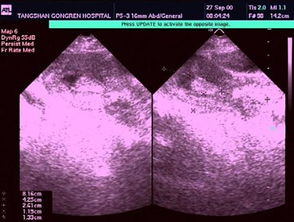

5、7天后是否要到醫(yī)院去復(fù)查B超?

大夫沒告你啊,做完刮宮的一周后要檢查的啊